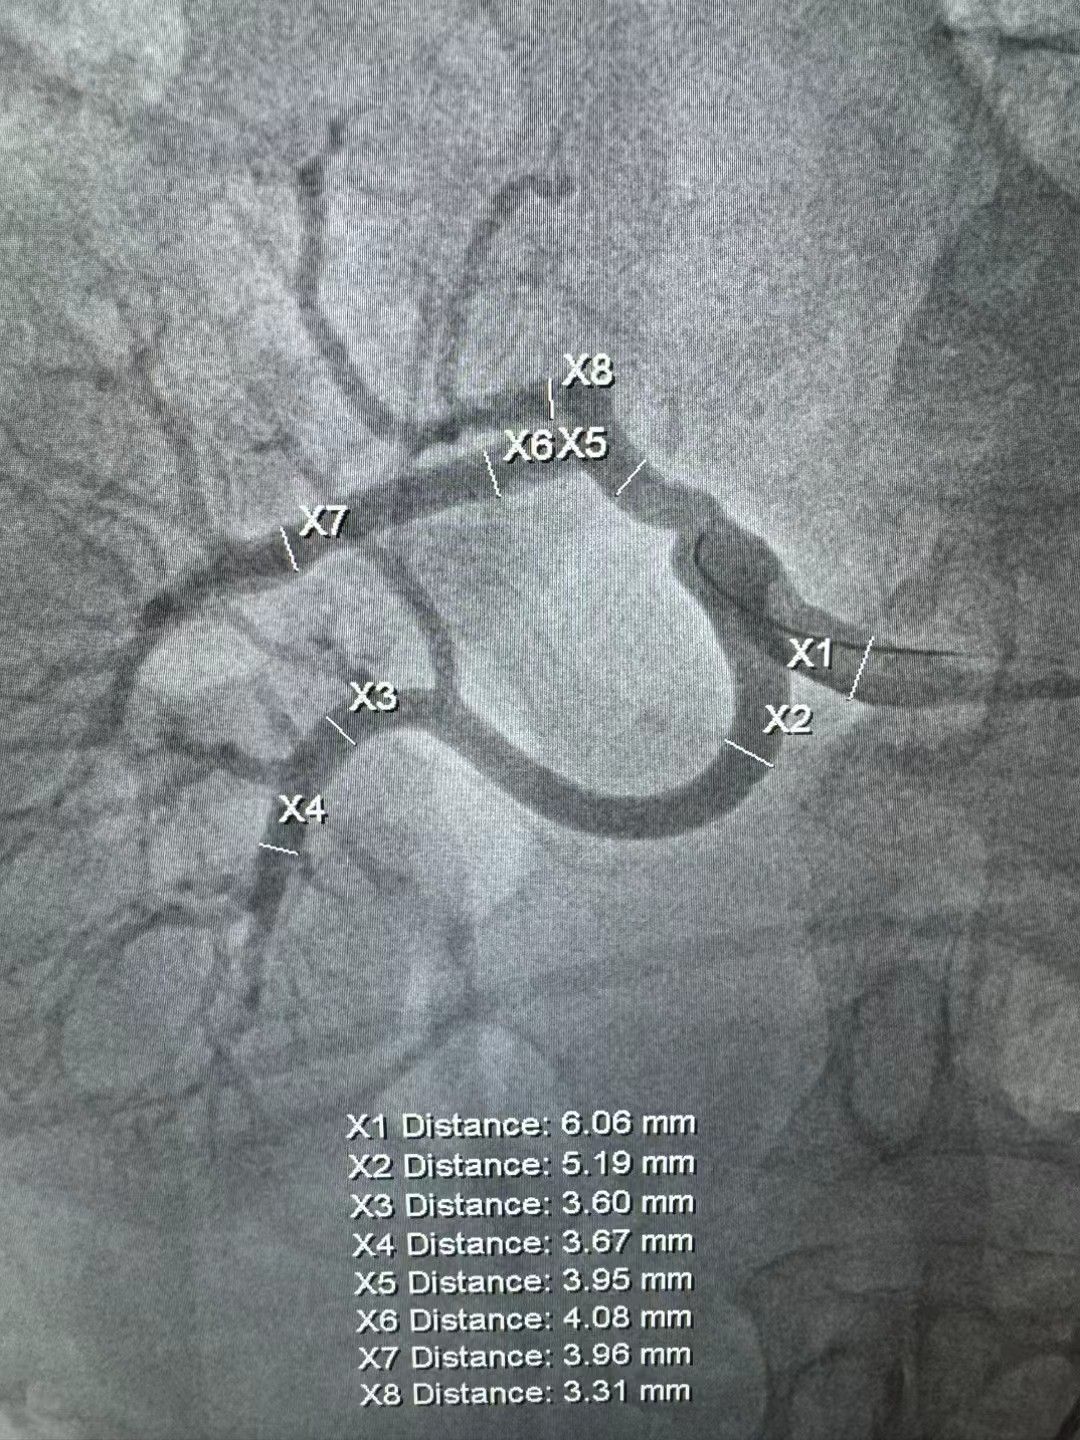

我中心现配有 20 余台医用智能化电子血压计,可实时传输血压数据;20余台 24 小时动态血压监测仪,具备多导心电图,动态心电图,动态血压监测,超声心动图,颈动脉超声多普勒,脉搏波传导速度,无创心功能检测,踝臂血压指数,尿微量蛋白,尿白蛋白定量,眼底检查,计算机断层扫描血管造影,心脏磁共振和动脉造影等检查设备条件和技术。此外,我院于2023年通过港澳药械通项目引入经皮肾动脉交感神经消融术(RDN)的微创手术,成为国内大陆地区首家批准开展RDN的医疗机构。同时开展的肾上腺静脉取血术以及肾动脉狭窄支架植入术等在继发性高血压诊治领域也取得良好效果。

肾动脉狭窄支架术